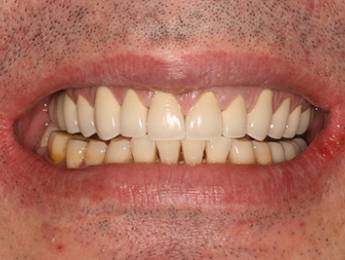

11. eset

27 éves páciensünk egész életében rettegett a fogorvosi beavatkozásoktól. Az összes foga elszuvasodott. A legkárosodottabb fogak gyökérkezelése és a szuvasodásainak megszűntetése után 26 fémkerámia koronát kapott a páciens. Erre a kezelésre is nagyon büszkék vagyunk. 2 hét leforgása alatt sikerült jelentős mértékben javítanunk a páciensünk mosolyán, önbizalmán és mióta velünk talalákozott, már a fogászati kezelésektől sem fél annyira!